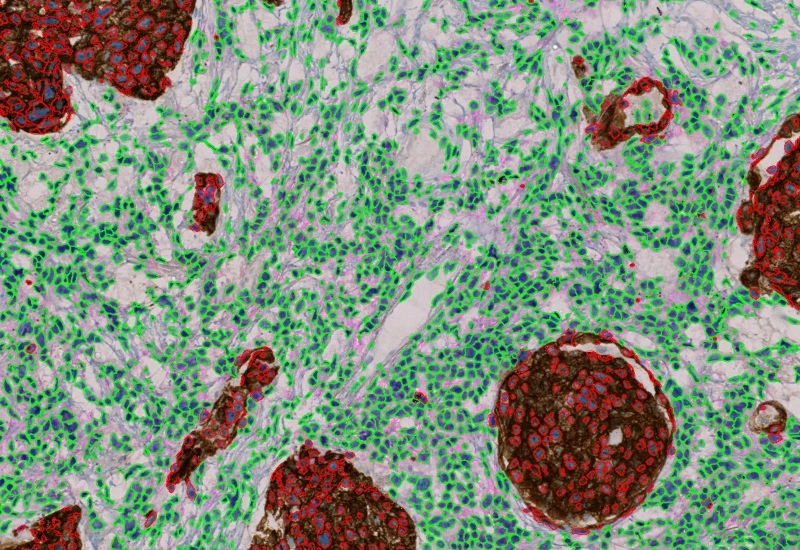

The IHC 3 App unmixes three markers (e.g. two chromogens and counterstain) in an IHC or HC digital slide and segments single cells into nucleus, and/or perinuclear area and/or cytoplasm. Each segmented cell compartment is measured for up to 20 intensity, statistic and morphometric parameters which are displayed in scattergrams and histograms and can be exported.

Marker 1-positive cells

Marker 2-positive cells